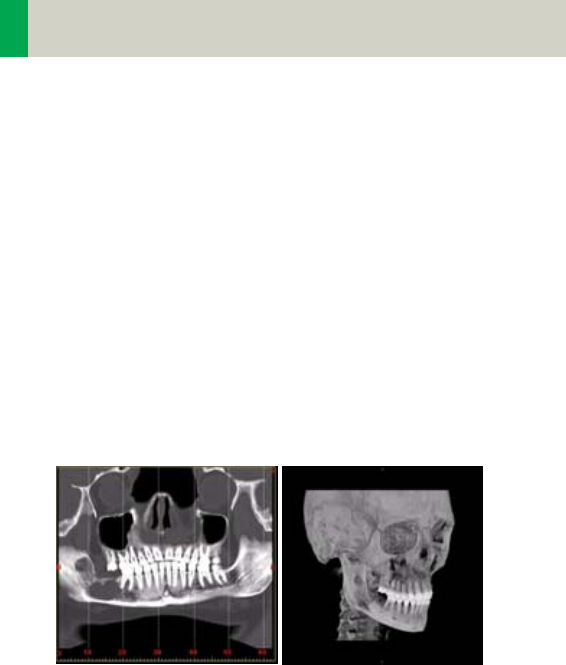

Case Examples for 3D Recon and Non-

Square Matrix

Some scan protocols are delivered with predefined

oblique and non-square matrix reconstructions.

These protocols are marked with the suffix “VOL”

•Coronal and sagittal reconstruction of the spine: